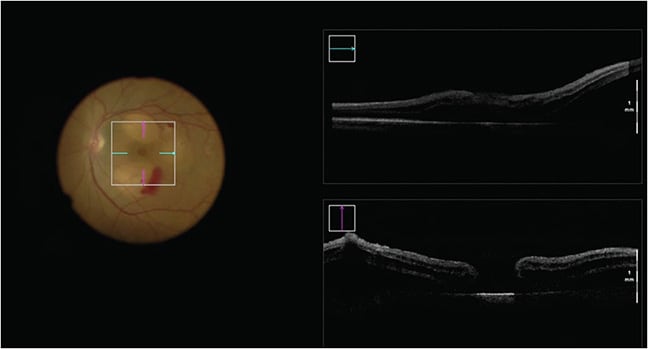

Mechanical manipulation of the retina with the goal of increasing tissue flexibility also facilitates the successful closure of MHs. Oliver and Wojcik first described this procedure in 2011.34 The technique relies on the creation of a controlled, localized macular detachment surrounding the MH using small-gauge cannulas (38-gauge or 41-gauge) connected to either a viscous fluid injection kit or syringe to administer balanced salt solution blebs contiguous with the MH (Figures 2 and 3). The edges of the MH can be brushed with a Tano diamond dusted scraper (Synergetics), a Flex Loop (Alcon), or a passive extrusion to further encourage closure. In some instances, to avoid creating additional defects in the retina, fluid can be refluxed through the macular hole into the subretinal space.35 The manipulation of the tissue is thought to release adhesions between the photoreceptors and retinal pigment epithelium, and may be particularly useful in situations with scarring which limits tissue mobility.34,36-38 Other methodologies rely on full-thickness retinal incisions. Charles et al first described an arcuate retinotomy technique, which requires full-thickness arcuate cuts temporal to the macular hole. Eighty-three percent of patients had successful closure of their MH and 50% had visual improvement.39 Other iterations of this protocol involve 5 perifoveal radial incisions, ending at the edge of the hole, or double arcuate relaxing retinotomies near the inferiortemporal and superotemporal arcades.40,41